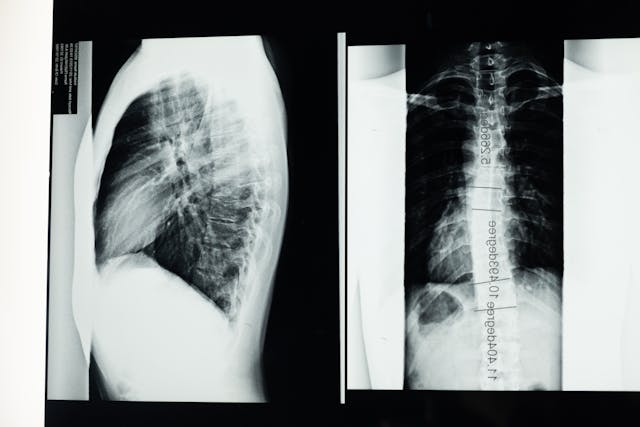

Důležitá je diagnostika

Asi nikdo nemá křišťálovou kouli, aby dokázal jasně předem říct, z čeho vás záda bolí. Proto je při dlouhodobějších potížích potřeba zajít k lékaři, kde podstoupíte i rentgen. Ten může ukázat nejen zakřivenou páteř, ale i spoustu dalších problémů, jako je třeba právě vyhřezlá ploténka. I tento problém se léčí obtížně, a způsobuje opravdu velké bolesti, které paralyzují celé tělo. Když už znáte diagnózu, je dobré se obrátit na fyzioterapeuta. Ten vám pomůže se správně hýbat. Možná vám to přijde zvláštní, ale problém může opravdu být i v tom, že se hrbíte a nebo nerovnoměrně přetěžujete záda. Dobrá zpráva je, že pokud nejde o velmi závažný stav, který musí být léčen operativně, máte šanci vyřešit svůj problém pomocí cvičení. Pokud vás trápí vyhřezlá ploténka a krční páteř, cviky pod dohledem fyzioterapeuta vám mohou pomoct.